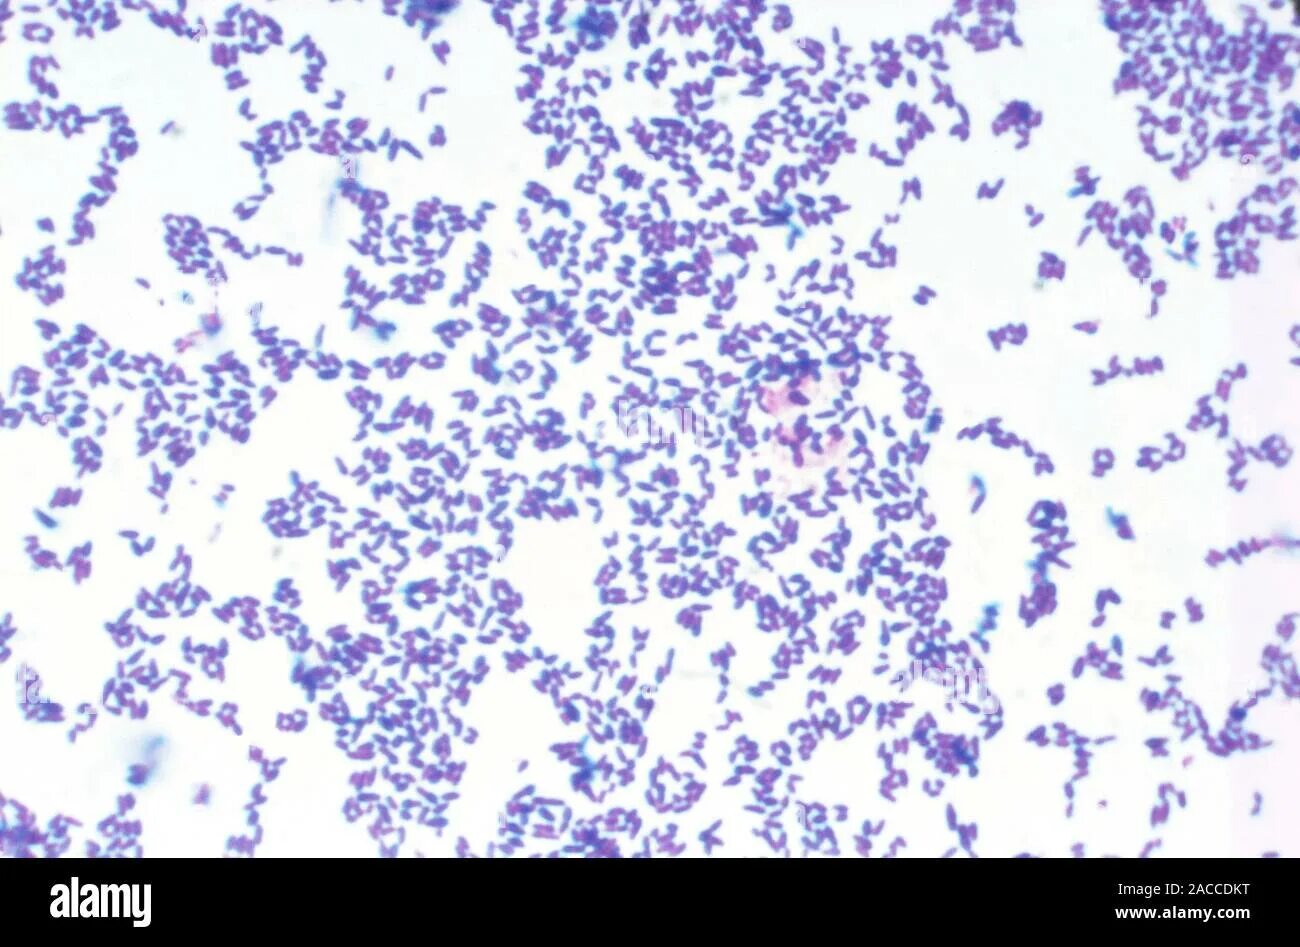

Mobiluncus spp corynebacterium в мазке